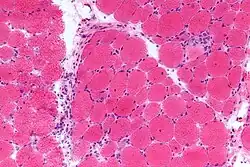

Mikrofoto von Dermatomyositis. HE-Färbung.

Die Dermatomyositis (DM, auch Lilakrankheit, Wagner-Unverricht-Syndrom) ist eine idiopathische Myopathie (Muskelerkrankung) bzw. Myositis (Muskelentzündung) (Idiopathische entzündliche Myopathie) mit Hautbeteiligung und gehört zur Gruppe der entzündlich-rheumatischen Erkrankungen, speziell der Kollagenosen. Ist nur die Muskulatur betroffen, so spricht man in der Regel von einer Polymyositis (PM). Aktuelle Studien zur Pathogenese der DM und PM widersprechen sich. Da noch nicht gesichert ist, ob DM und PM die gleiche Pathogenese haben, wird im Folgenden die Dermatomyositis getrennt besprochen und auf die Polymyositis sei nur verwiesen.